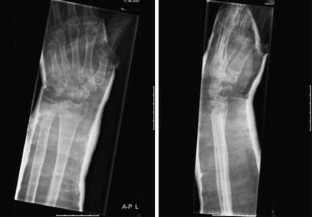

Fig. 3

Distal radius fractures are one of the most common fractures in the elderly females. In this article, we report a case of a distal radius fracture type AO-A3 with dorsal instability, in an older woman with manifest osteoporosis, treated with minimally invasive Cortoss® composite and FFS-wires®. A 63-year-old woman sustained an unstable distal radial fracture of her left wrist after falling from a kitchen step. She underwent an open reduction of the fracture and fixation with two crossed-fixation pins and Cortoss® composite. Post-operative plaster cast immobilization was given for 2 weeks, after which the plaster cast and the fixation pins were removed. At 4 weeks follow-up, she had a good functional result of her left wrist, after 11 months there was a complete return of grip strength with also, except for the palmar flexion, a full return of function. We report here the first case of a successful surgical treatment with Cortoss® composite of an AO-A3 type distal radius fracture.